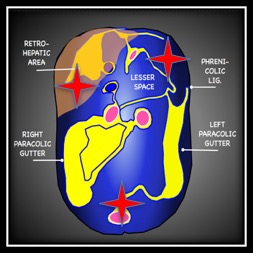

Fluid flows downhill and respects boundaries – it must build up in one area before overflowing to an adjacent area. This seems simple but in the context of the FAST exam it relies on a comfort with somewhat abstract anatomy.

To simplify things, I think of a body lying supine with all of the peritoneal organs removed except for the liver – which must remain as it is tethered to the diaphragm. What you have is the smooth contour of the retroperitoneum and its reflections:

Now we have to consider some other factors, the bladder limits the amount of fluid that can fit in the pelvis so this quickly spills over the pelvic brim.

In order to reach the upper peritoneum fluid from the pelvis must travel along one of the paracolic gutters, the left paracolic gutter is relatively higher than the right and flow is limited by the phrenicolic ligaments so pelvic fluid almost always spreads first to the caudal tip of the liver in the RUQ.

The spleen is the most common source of hemoperitoneum in trauma, and unlike the liver it is small and untethered allowing blood to collect beneath it. This is the reason for emphasizing the ‘6 to 9 o-clock’ view in the LUQ. This is often the first and only place blood can be seen in a serious splenic injury. When explaining this to juniors it can help to reference a coronal slice of a CT. This video shows the superimposition of the US image on the CT. Note how much of this splenic bleed is invisible to the initial view.

It helps understand where the 6-9 o clock position actually is and helps explain why interrogation of this deep recess is so important.